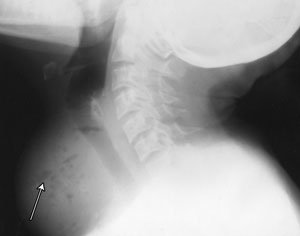

A 40-year-old woman presented with sudden onset of a painful neck swelling, fever and dysphagia. Examination revealed a warm, tender lump in her thyroid gland. Five weeks previously, she had had an abdominal hysterectomy with bilateral salpingo-oophorectomy for pelvic inflammatory disease. There was no evidence of leukopenia or diabetes. Computed tomography and x-ray images were consistent with a diagnosis of thyroid abscess (Figure 1 and Figure 2).